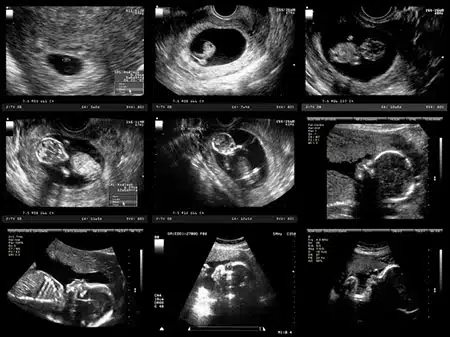

Your Baby's Amazing Journey Within You!

From Tiny Spark to Beating Heart:

The very first sign of life is a tiny flicker –your baby’s heart starts pumping blood as early as 3 weeks after conception (that’s when the sperm meets the egg!). It might be too small to hear yet, but by 7 or 8 weeks (about 2 months), a special tool called an ultrasound stethoscope can pick up that little heartbeat.

As your baby is growing, the baby’s brain starts working super early, as early as 8 weeks! That’s around the same time the eyes, ears, and even the breathing system begin taking shape. It’s like a mini construction zone in there! By 8 weeks, all your baby’s major organs are there, and the tiny tummy even starts making juices to help digest food.

This might surprise you, but the buds for all 20 baby teeth are present by 6½ weeks! They are very tiny teeth, but they’re there. Fingernails start appearing around 11-12 weeks (about 3 months), and by 16 weeks (about 3 and a half months), even eyelashes start sprouting. As early as 9 or 10 weeks (about 2 and a half months), the baby can even make some wiggly moves – like squinting, swallowing, and even making a tiny fist!

Once she saw her baby on the ultrasound, she realized it wasn’t just a mass of cells. It was formed and organized. And while it didn’t look like a fully formed baby just yet, it was clear to see that it was on its way to becoming something. It was at that moment that Tara realized that ending her baby’s life simply to avoid telling her parents was not the answer.